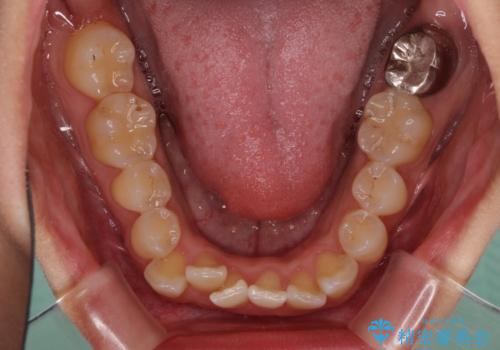

前歯のデコボコをインビザラインでスッキリと仕上げる

- 上下前歯のデコボコと奥歯の銀歯を気にして来院された患者様です。

口元をインビザラインにより歯列を整え、その後に失活している奥歯をオールセラミッククラウンにて補綴治療することとしました。

長時間のマウスピース装着に協力いただき、自然な口元に仕上げることができました。

気になっていた銀歯もオールセラミッククラウンで本物の歯のようになり、患者様には大変満足していただきました。